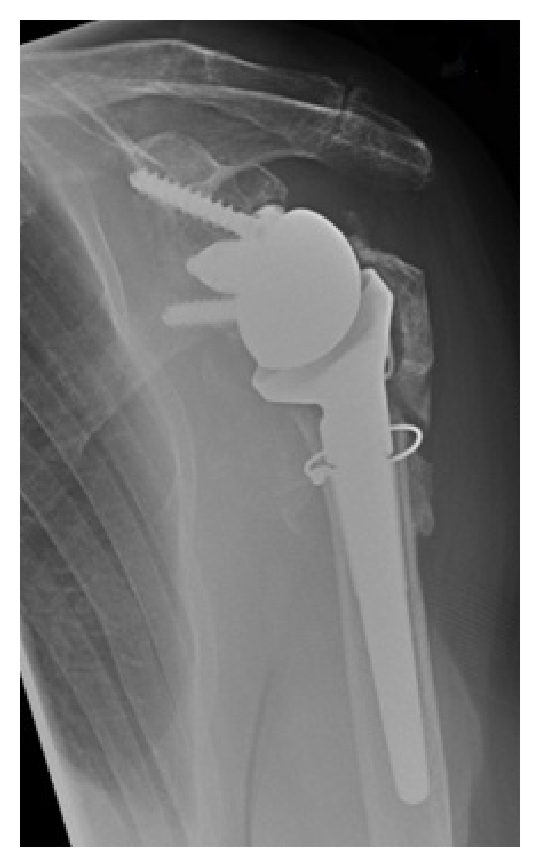

Her standard orthopaedic follow-up for her reverse-geometry shoulder replacement was unremarkable with an excellent range of movement achieved at 8 weeks with satisfactory radiographs (Figure 4) and she was discharged at the 6-month stage.

(a)

(b)